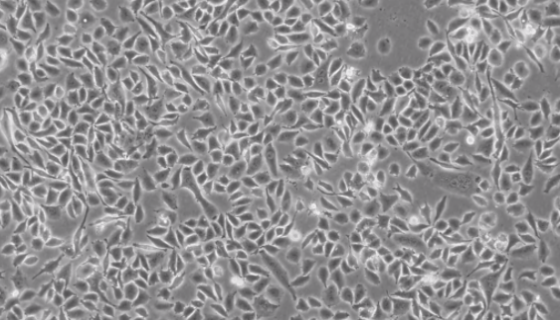

RKO人结肠腺癌细胞的培养步骤与应用!

RKO人结肠腺癌细胞是一个低分化的结肠癌细胞系。RKO细胞含...